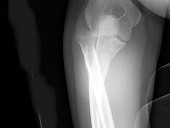

- 单项选择题女,55岁, 跌倒后右手痛,结合X线平片表现, 正确的诊断是 ( )

A、柯莱斯骨折

B、蒙泰贾骨折

C、加莱阿齐骨折

D、尺桡骨骨折

E、反柯莱阿齐骨折